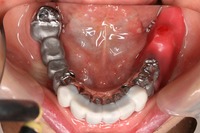

まず、内冠を患者さんの歯に仮止めしてから、その上に外冠を合わせて、噛み合わせを見ます。

リーゲルレバー(閂カンヌキ又はスイングロックとも言う)を開いたところです。

外冠を取り外すことができます。

リーゲルレバーを閉じたところです。

お口にしっかりと固定され、びくともせずにしっかりと咬むことが出来ます。